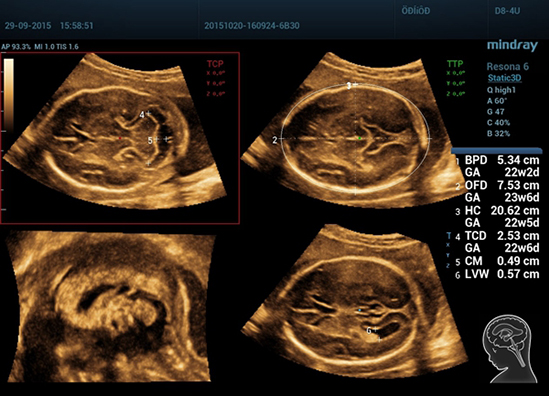

Smart Planes

Благодаря уникальной новаторской технологии компании Mindray, система Resona 6 является новейшей системой ультразвуковых исследований, обеспечивающей полностью автоматическое и точное получение особо важных проекций и проведение наиболее часто используемых измерений ЦНС плода, что обусловливает интеллектуальную диагностику, улучшение производительности и снижение зависимости от пользователя.

Smart Planes — это удобный для пользователя инструмент, значительно повышающий эффективность сканирования за счет увеличения точности в сочетании с автоматизацией работы. Одного нажатия на клавишу достаточно, чтобы из 3D данных, полученных при сканировании мозга плода, немедленно получить стандартные плоскости сканирования ЦНС: MSP (медиальная сагиттальная плоскость), TCP (трансцеребральная плоскость), TTP (трансталамическая плоскость) и TVP (трансвентрикулярная плоскость), а также получаемые в них измерения (БПР, ОГ, ЛЗР, Поперечный Диаметр Мозжечка, Большая Цистерна и Ширина Бокового Желудочка).

1-R6-img9